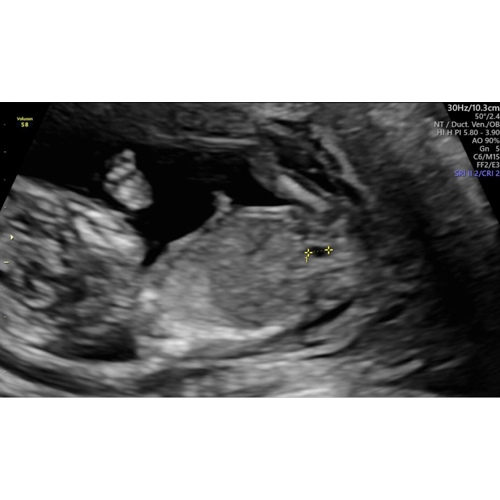

Wat denken jullie? Hier is mijn vrouw 12+4

Goedemorgen, wat denk je bij deze echo? 14w

Hi Nubster, dit was 12 weken. Ben benieuwd 🙊

Hi, nog steeds een 💗? 13+3